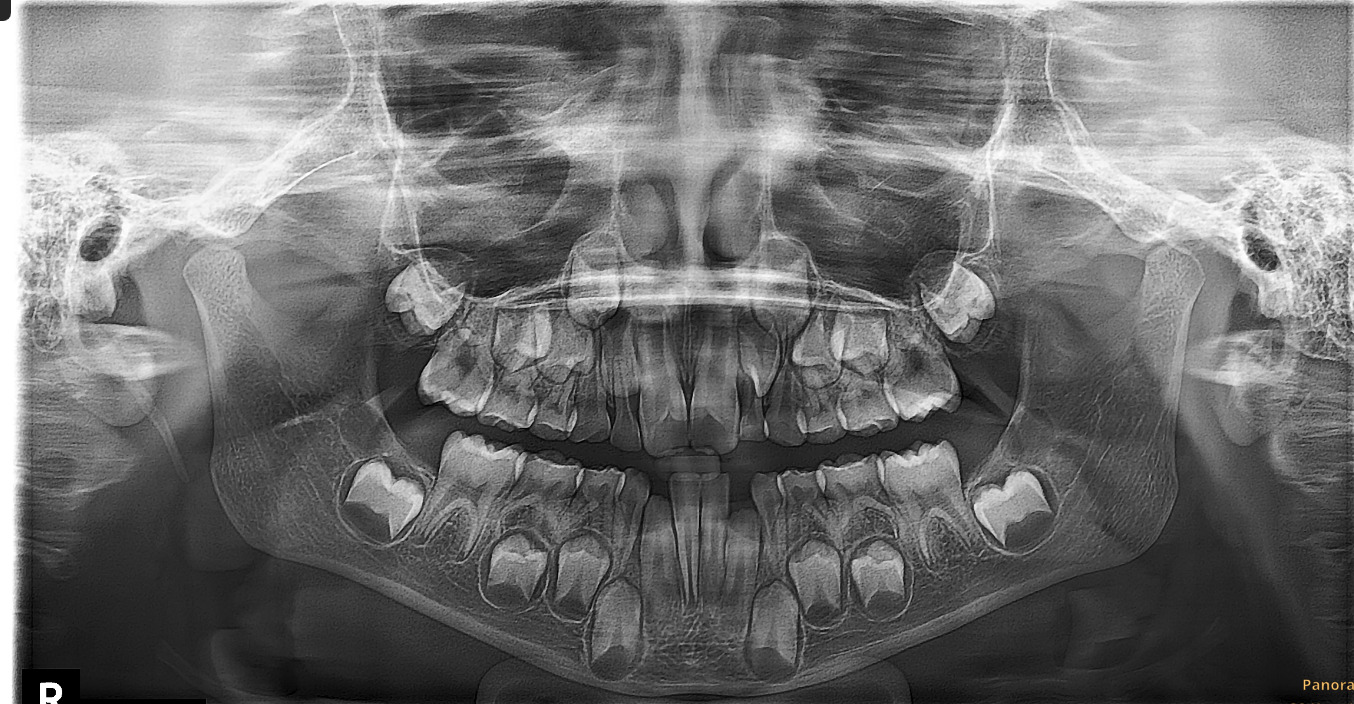

Медицинские Исследования: Кортикальная Пластинка на ОПТГ